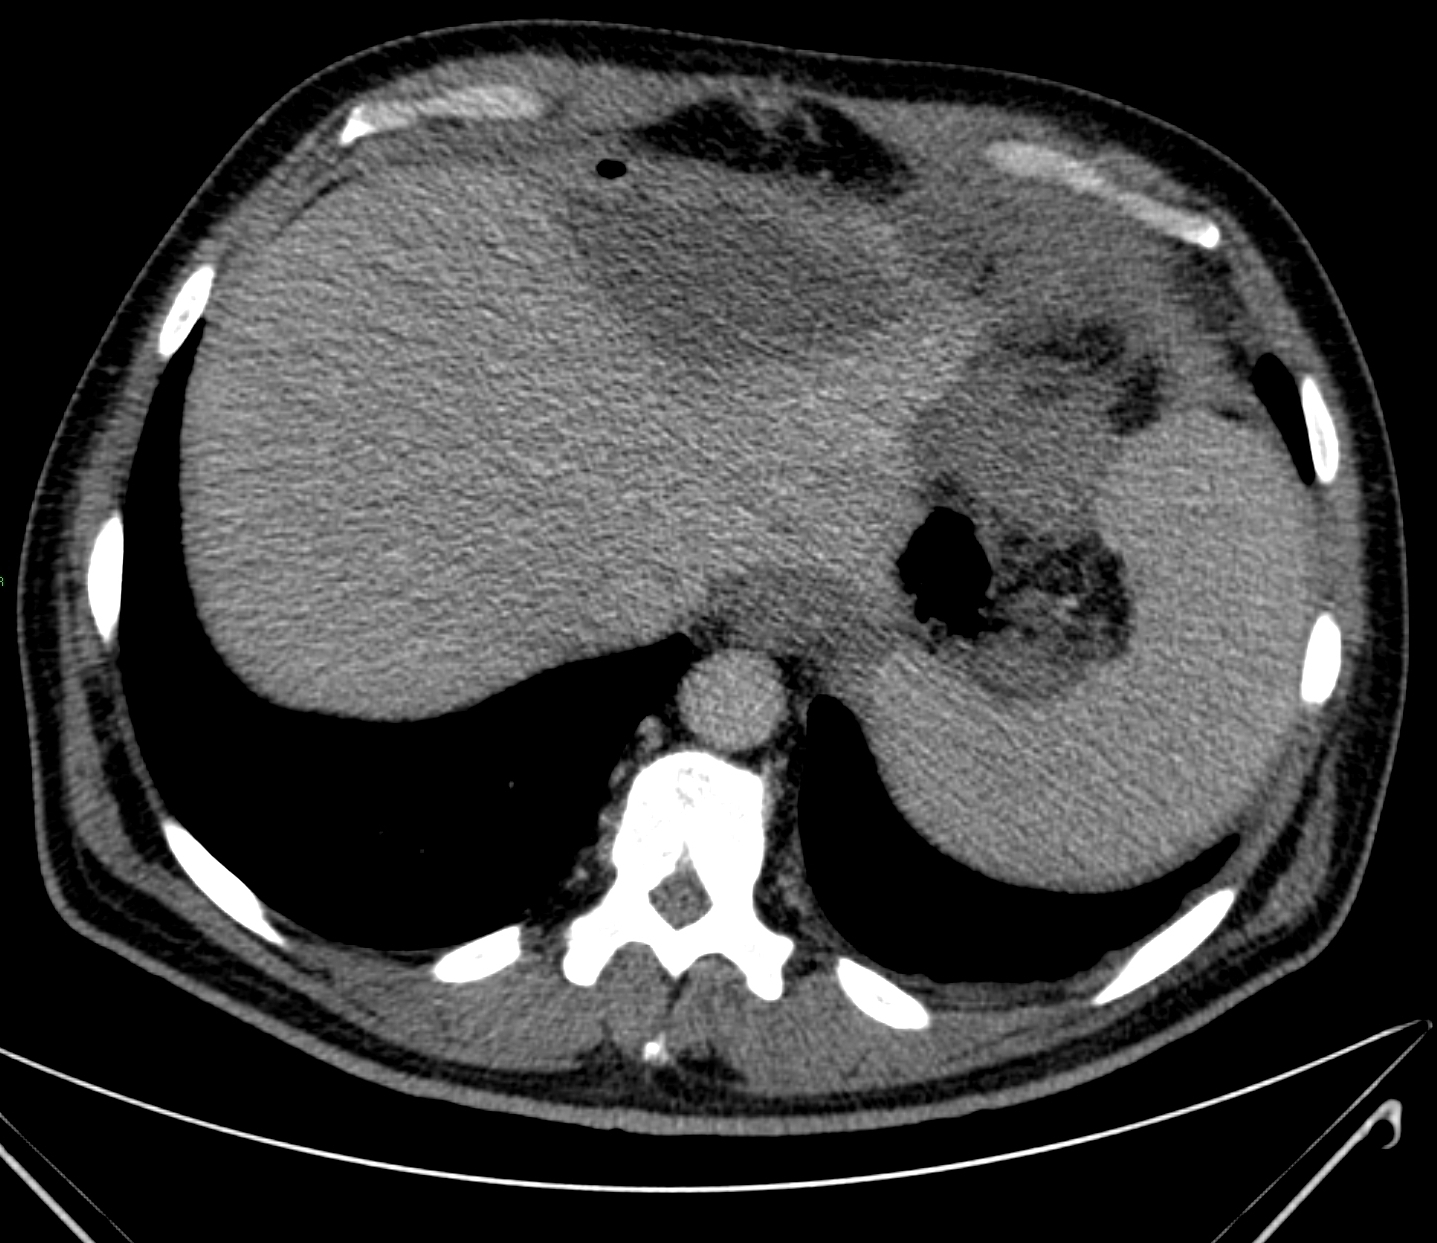

Liver abscess can develop either following the severe inflammation of the biliary ducts and the gallbladder or following a tumorous necrosis or by the spread of an external inflammation to the liver. By the help of the US, a cystic lesion can be seen with multiple internal echos containing gas bubble frequently as well. In order to determinate the further therapy, contrast enhanced CT examination can be needed, if the US imaging of the entire liver was not possible. An avascular intrahepatic lesion can be seen well on the CT with a contrast enhancing wall (sometimes multifocal as well) (Figure 30). An US or CT guided percutaneous drainage can provide a therapeutic result depending on the lesion's size and location (Figure 31).

Figure 30: Abscess in the liver, native CT